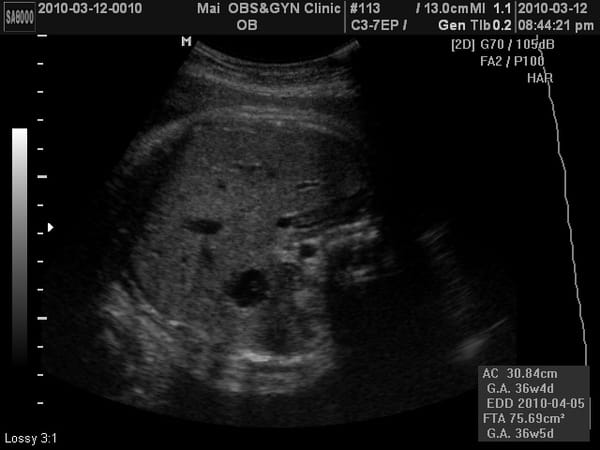

小老虎上次產檢2050公克,這次2500公克,果然到了最後階段胎兒是以爆量在增長的。

這兩次的產檢醫生比較注重在"頭小"了兩周的議題上,這次還說了「小腦症」這個名詞,可是跟上次比起來頭也明顯跟著長了兩周,又不像~